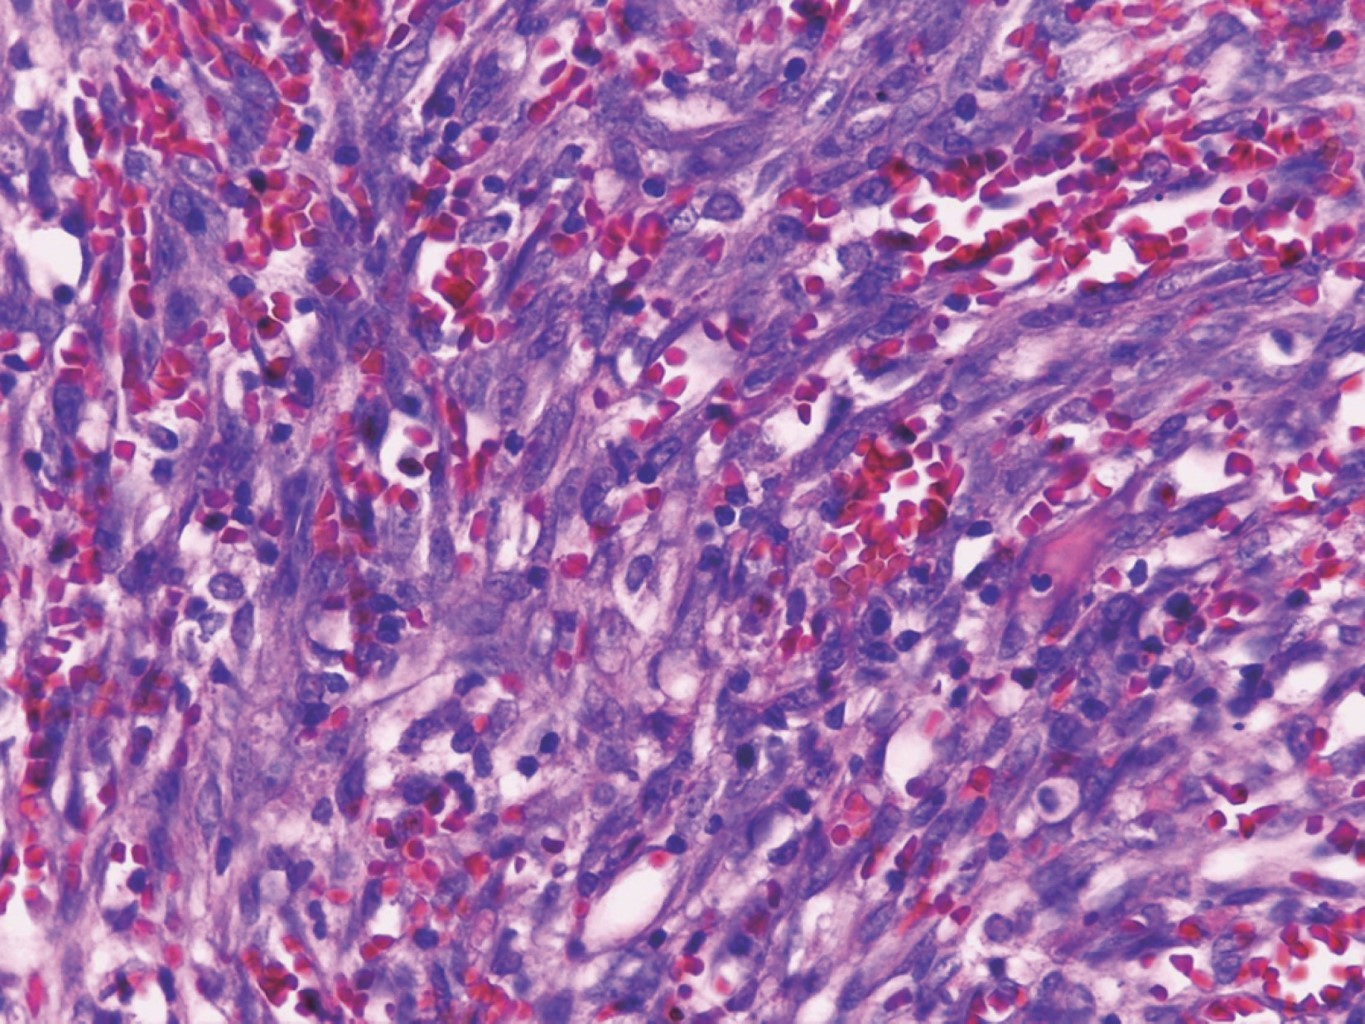

El tratamiento fue mediante escisión por rasurado y electrocauterización (Figura 4). En el estudio histológico se observó una neoformación exofítica cuya epidermis presenta hiperqueratosis paraqueratósica focal, atrofia y zonas ulceradas. En el espesor de la dermis se observan numerosos vasos neoformados dilatados y congestionados cuya pared se encontró formada por una sola hilera de células endoteliales, los cuales se entremezclan con numerosas células fusiformes que siguen diversos trayectos inmersos en un estroma edematoso (Figuras 5, 6 y 7).

El diagnóstico es clínico, pero es necesario confirmarlo por estudio histopatológico en el cual se observan células fusiformes, proliferación de vasos irregulares con hendiduras vasculares, extravasación de hematíes, e infiltrado leucoplasmocitario y glóbulos hialinos intra y extracelulares, así como el característico signo del promontorio. La PCR y la inmunohistoquímica para la detección del antígeno nuclear asociado a latencia (LANA-1) del virus VHH-8 son positivos.9

Figura 5

Figura 6

Figura 7